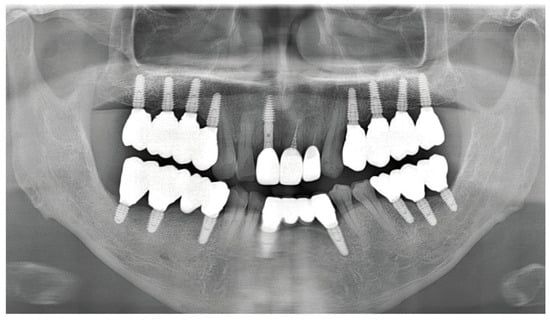

As part of the patient’s ongoing maintenance therapy, follow-up examinations were conducted every six months with routine dental plaque control. When required, additional periodontal treatment was provided during subsequent visits. Annual panoramic radiographs were taken to monitor the long-term prognosis of the implant. At the two-year follow-up, the implant prosthesis remained well maintained and functionally stable within the oral cavity (Figure 11).

Figure 11.

Panoramic radiograph after 2 years.

As ongoing maintenance, six-monthly follow-ups with dental plaque control were conducted. Additional periodontal treatment was provided as required. Annual panoramic radiographs were obtained to monitor implant prognosis. At the two-year follow-up, the implant prosthesis remained stable (Figure 15).

Figure 15.